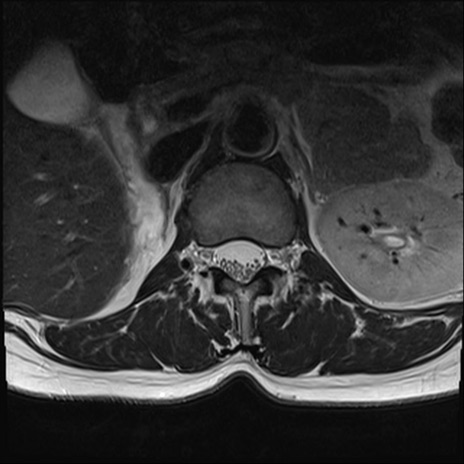

【整形】TIPS症例4 腰椎MRI T2WI(横断像)

腰椎MRI

横断像と矢状断像